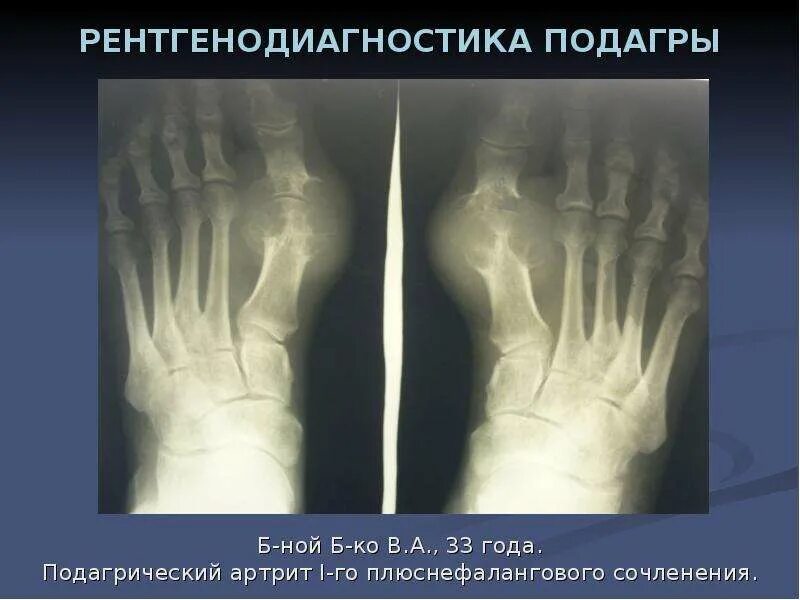

Артроз плюснефалангового сустава стопы